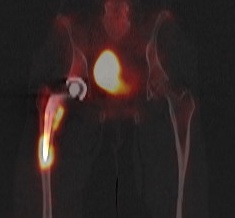

PET scan / [18F]Fluoro-2-deoxyglucose positron emission tomography (FDG-PET)

Kwee et al Eur J Nucl Med Mol Imaging 2008

- meta-analysis 11 studies and 600 patients

- 82% sensitive and 87% specific